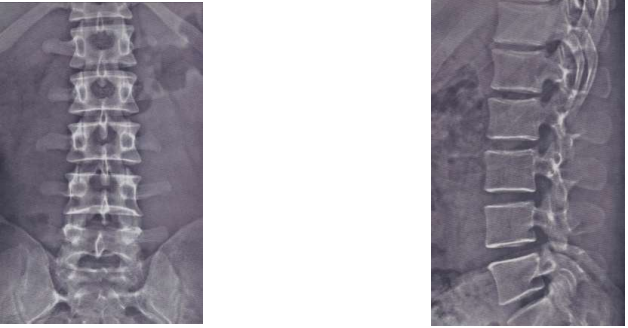

Wirbelsäule

7 Halswirbel

12 Brustwirbel

5 Lendenwirbel

Kreuzbein & Steißbein

Besonderheit Wirbelsäule

Stützorgan

Beweglichkeit nötig

Gewicht des Körper abpuffern

S-Form

Halslordose → Biegung nach vorne

Brustkyphose → gegenläufige Biegung

Lendenlordose

Kreuz-/Steißbeinkyphose

Bandscheibe

äußere fibröser Faserring

Bandscheibenkern (Gallertkern)